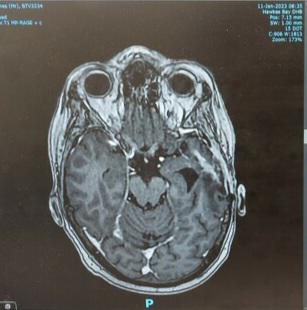

Main image

This photo was taken on the 8th April 2021, two days post surgery, when our lives were turned upside down.